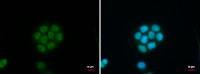

IHC-P analysis of human breast carcinoma tissue using GTX87771 KCNAB3 antibody. The picture on the right is blocked with the synthesized peptide.